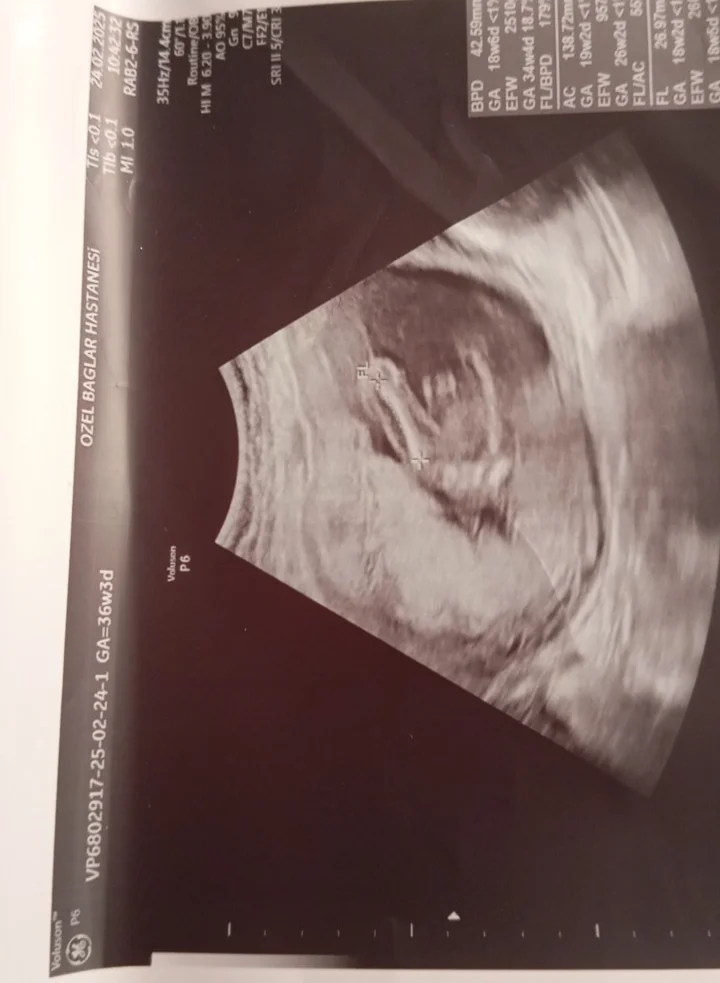

Bunada bakar mısınızKese yuvarlak kız gibi

Başka foto var mı iki bacak arası gibi bu ama bulanık çıkmış gördüğüm çıkıntıysa erkek ama emin olamadımBunada bakar mısınız

Bunlar var canimBaşka foto var mı iki bacak arası gibi bu ama bulanık çıkmış gördüğüm çıkıntıysa erkek ama emin olamadım

Bunada bakar mısınız 11

KızBunada bakar mısınız 11

Başka foto var mı iki bacak arası gibi bu ama bulanık çıkmış gördüğüm çıkıntıysa erkek ama emin olamadım